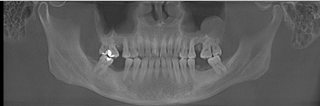

麦芽口腔中方院长对王先生的口腔ct片进行专业深度的分析之后,决定为其种植麦芽数字化生物种植牙,“麦芽数字化生物种植牙”,运用数字化、纳米、微痛、保证口腔功能重建和舒适修复的同时,兼顾口腔美学修复,既能快速修复牙齿,恢复咀嚼,同时能够达到较好的美观程度,术中采用STA美国微痛麻醉,确保了手术全程的舒适度,且采用数字化3D种植导板技术,能够更加准确、更加快速找到最佳植入位置,有效避免手术过程遭受痛苦,保证了手术成功率。